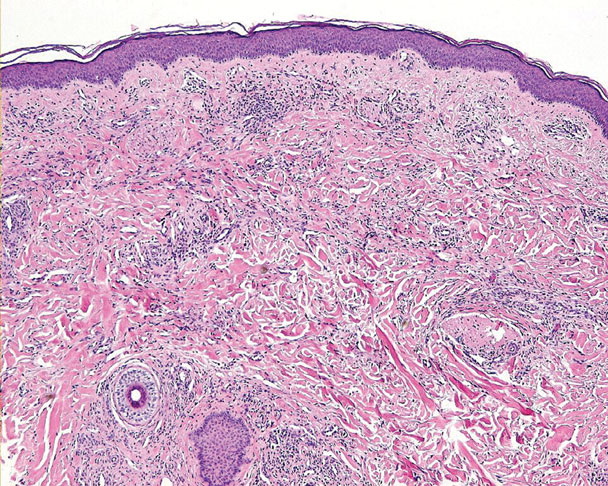

HISTOPATHOLOGY

The histopathology of KS is dependent on the stage of KS development. Early patch-like lesions exhibit rather discrete histopathologic changes, consisting mainly of an increase in the number of dermal vessels, outlined by slightly irregular endothelial cells (Fig. 128-5). These vessels, located mainly in the superficial dermis are parallel to the skin surface, are frequently slightly irregular, and may form bizarre slits and clefts. In the surrounding skin focal hemosiderin, deposits and extravasated erythrocytes can be found as well as a moderate inflammatory infiltrate. Important differential diagnoses of this stage include lymphangioma and granulation tissue.

The pathology of KS plaques is more characteristic and reveals extensive vascular proliferation at all levels of the dermis with multiple dilated and angulated vascular spaces dissecting the collagen leaving a spongy network of collagen tissue. A characteristic sign of KS papules is the presence of solid cords and fascicles of spindle cells arranged between the jagged vascular channels. This biphasic angiomatous and solid tumor morphology changes to a clear-cut sarcomatous morphology with progression of the disease.

Nodular lesions consist predominantly of spindle cells arranged in bundles and interlacing fascicles and interspersed, irregular, slit-like vascular spaces without endothelial linings. Advanced lesions may display pronounced pleomorphism, nuclear atypia, and mitotic figures. At the periphery of solid tumors, (lymph) angiomatous-like portions of KS with bizarre vascular lumina and intravascular and extravasated erythrocytes, as well as siderophages, may be preserved. Erythrocytes, which appear as eosinophilic globules, are trapped within the slits and clefts formed by the spindle cells and erythrophagocytosis are occasionally observed. As in all other stages of KS, a moderate inflammatory infiltrate consisting of lymphocytes, histiocytes, plasma cells, and, sporadically, neutrophils is regularly present.